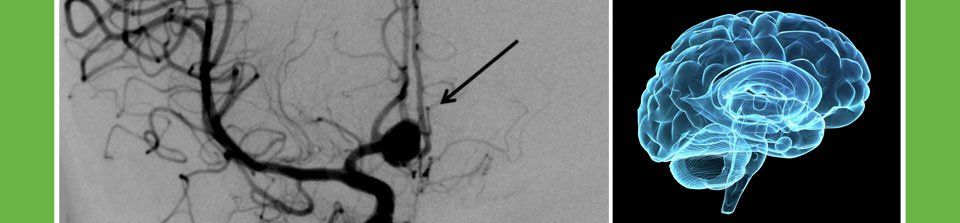

¿Qué es la Neurocirugía Endovascular?

Cirugía de mínima invasión que se realiza a través de las arterias y venas del cuerpo para el tratamiento de patologías como aneurismas cerebrales, malformaciones arteriovenosas cerebrales y medulares, tumores hipervascularizados cráneo cervicales y el tratamiento del accidente cerebrovascular (acv o derrame cerebral) isquémico y hemorrágico.